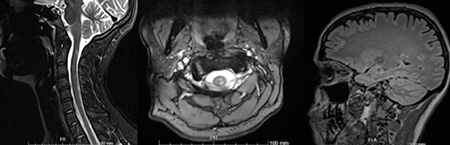

Ressonância magnética

• Área de hipersinal nas sequências de TR longo no cordão posterior esquerdo face ao dente do axis, passível de traduzir lesão inflamatória. Gd-

• Foco de hipersinal no hemisfério cerebeloso esquerdo, de natureza indeterminada

• Hipersinal nas ponderações TR longo, sugestivos de lesões desmielinizantes

• periventricular no corno temporal direito e frontal ipsilateral

• no corpo do corpo caloso à direita

• justacortical parietal superior esquerda

• interface caloso-septal de muito pequenas dimensões direito

• pequeno foco de hipersinal no cone medular paramediano direito